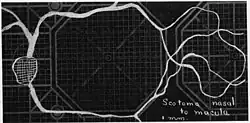

Using eccentric fixation, the more nasal parts of the angioscotoma can be plotted.

Using eccentric fixation, the more nasal parts of the angioscotoma can be plotted. -